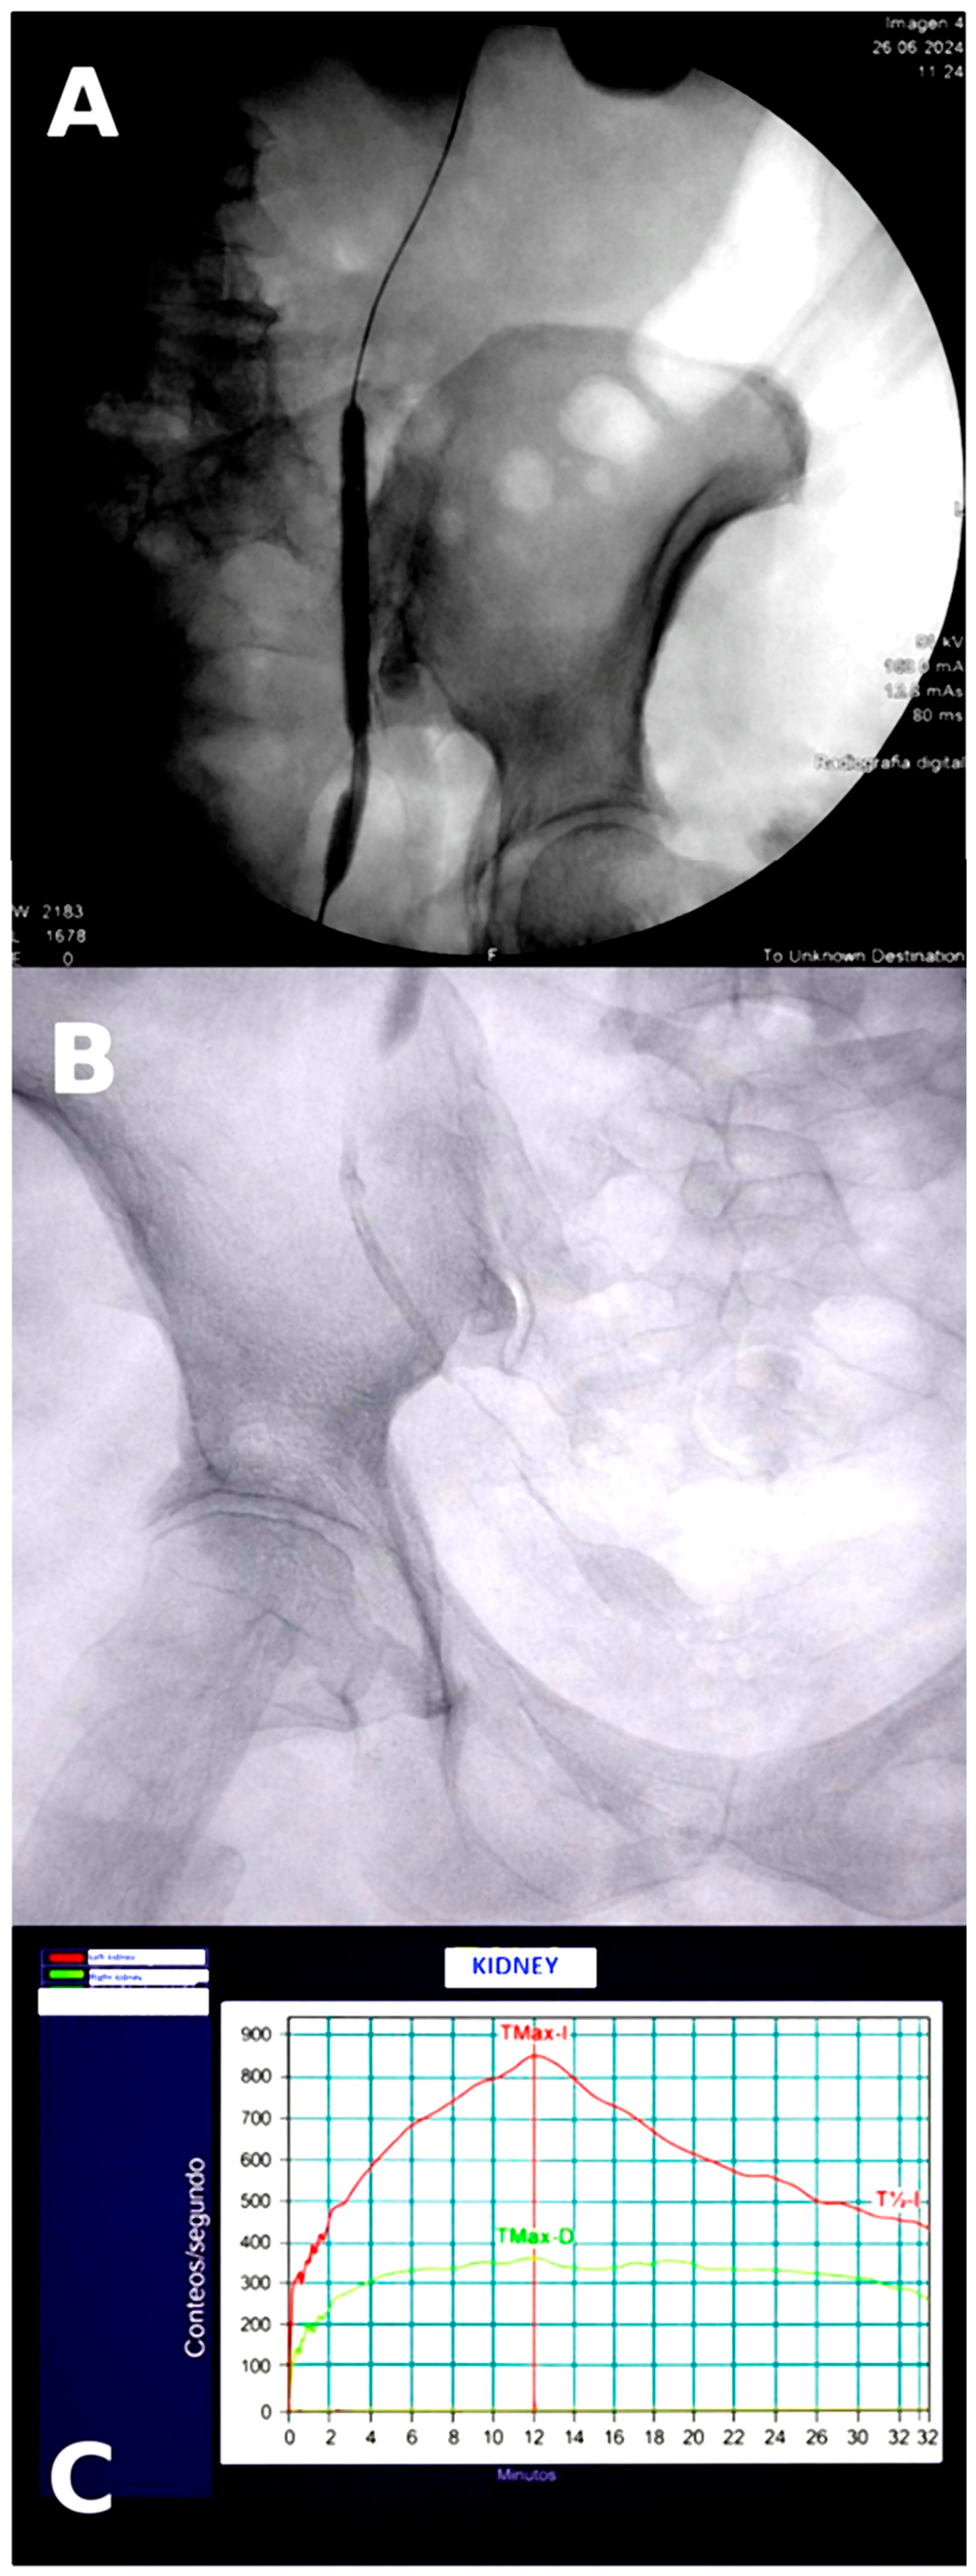

| Apr 2024 | Follow-up evaluation | DJ + nephrostomy (left) | CT: persistent hydronephrosis; renogram: obstruction | Left 41.7%/Right 58.3% |

| May 2024 | Balloon dilation | DJ stent (left) | Stricture ~1 cm | — |

| Oct 2024 | Combined pyelography | Nephrostomy | Distal stricture 2.5 cm | — |